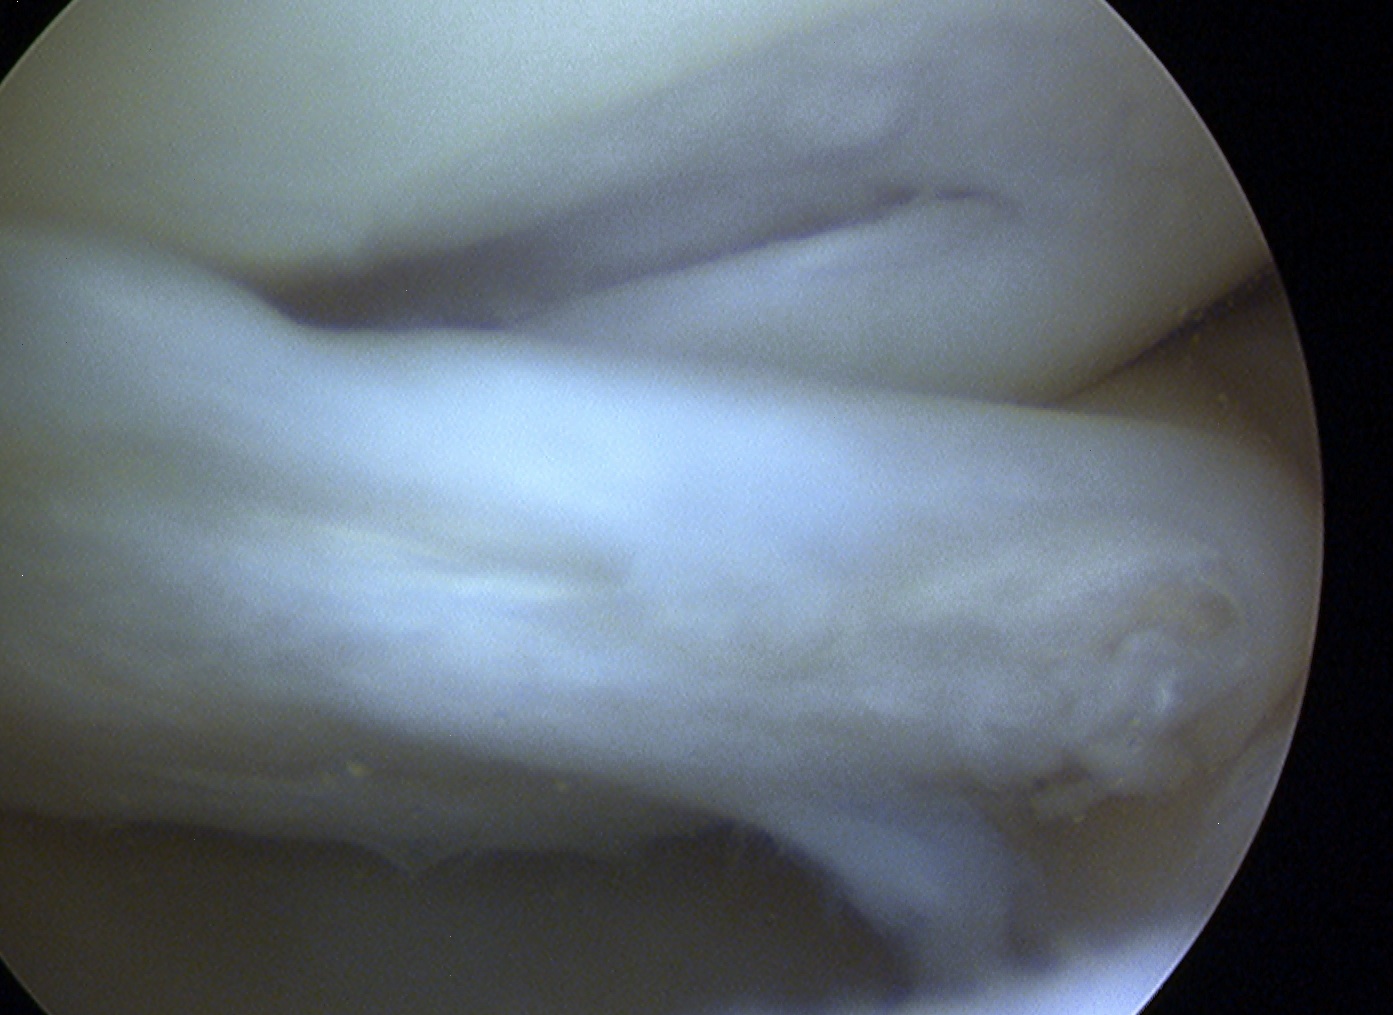

Arthroscopy

Mainstay of diagnosis and treatment

C. Bucket handle

- displaces into intercondylar notch

- may be central or peripheral

- cause of locked knee

- can damage chondral surface over time

Signs of bucket handle tear meniscus

1. Double PCL sign

- medial Meniscus

2. Absent bow tie sign

- should see bow tie image on 2 consecutive sagittal slices of 5 mm

3. Fragment in notch sign

4. Anterior flipped meniscal sign

- torn fragment flips over the anterior horn of the affected meniscus

5. Truncated meniscus